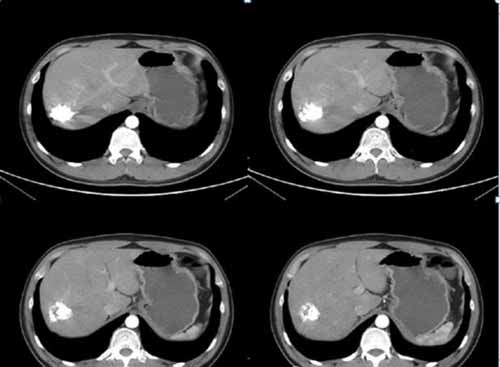

(手術(shù)過程:通過DSA下動脈造影,找到供血動脈,注入栓塞劑進行栓塞。)